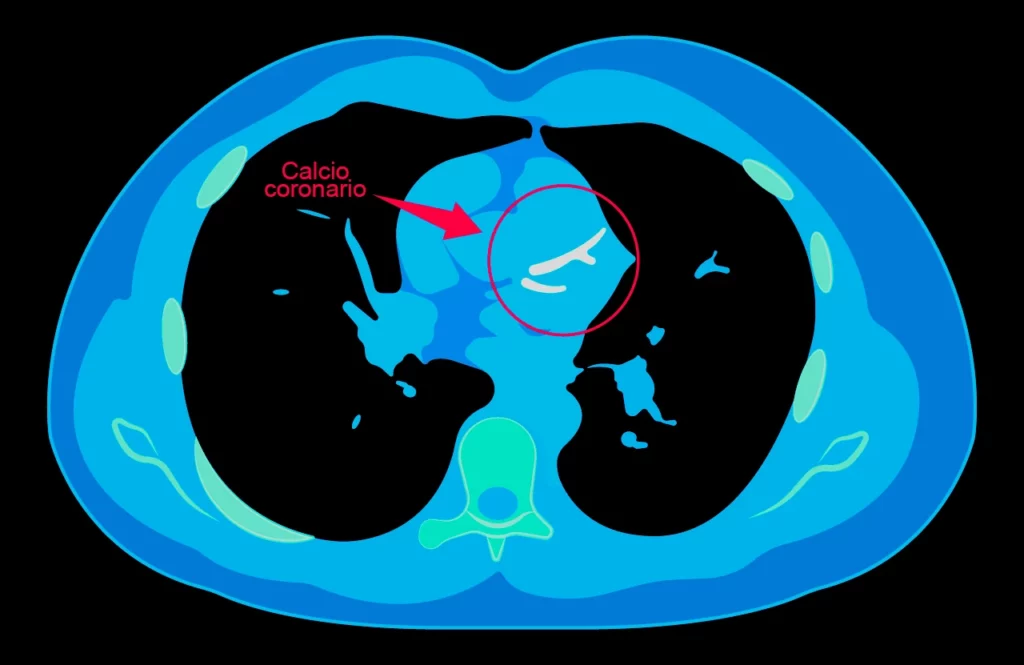

Imagen de score de calcio coronario realizado donde analiza una arteria coronaria para detectar el riesgo de infarto.

El score de calcio coronario es un estudio de imagen que se realiza de una manera sencilla, mediante una tomografía que permite conocer el índice de calcio coronario.

Mediante el estudio de tomografía para índice de calcio coronario se podrá detectar si se está depositando calcio en las paredes de las arterias y, realizando este estudio en tiempo, se conocerá y, por ende, se actuará para detener dicha acumulación.